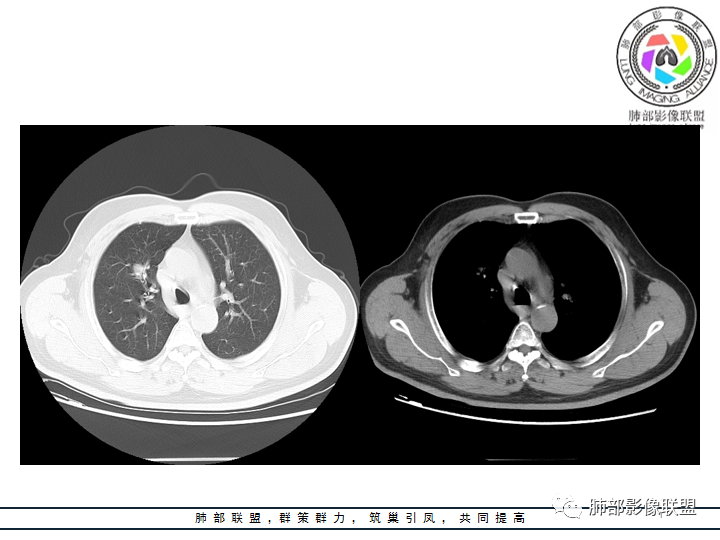

老年男性患者,长期吸烟史,没有呼吸系统临床表现。胸部CT示右肺上叶实性密度结节影,密度均匀,未见空洞及钙化,边缘较光整,未见分叶及毛刺。血管影旁现侧出,支气管进入并截断,不均匀强化。

边缘光整,干净游离,密度均匀,没有钙化及空洞,没有卫星灶,PPD皮试(-)等,不符合结核球。

恶性病灶需要排除的有神经内分泌癌(大细胞癌、小细胞癌、类癌)、鳞癌、淋巴瘤样上皮癌、淋巴瘤等等。

——本例鳞癌病理意见可以符合,只是太光整、太干净,且病灶不大,未能显示出坏死等特征,我们从影像上难以得出倾向性意见。